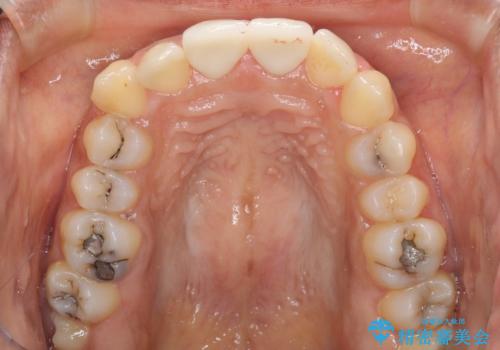

- 上の前歯2本の審美障害を気にして来院された患者様です。樹脂が無造作に充填されており、色合いも形態も不自然で、歯肉も腫れているため、オールセラミッククラウンにて補綴することとしました。

充填されたレジンを取り除いたところ、歯肉の炎症による出血が認められました。セラミッククラウン装着後は歯肉が腫れることもなく、仕上がりも自然な歯のようになり、患者様には大変満足していただきました。